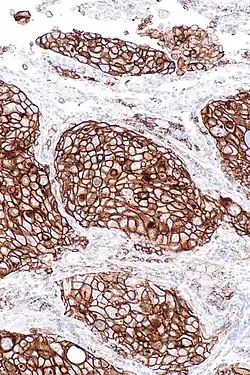

| Micrograph of a squamous carcinoma, a type of non-small-cell lung carcinoma, FNA specimen, Pap stain. | |